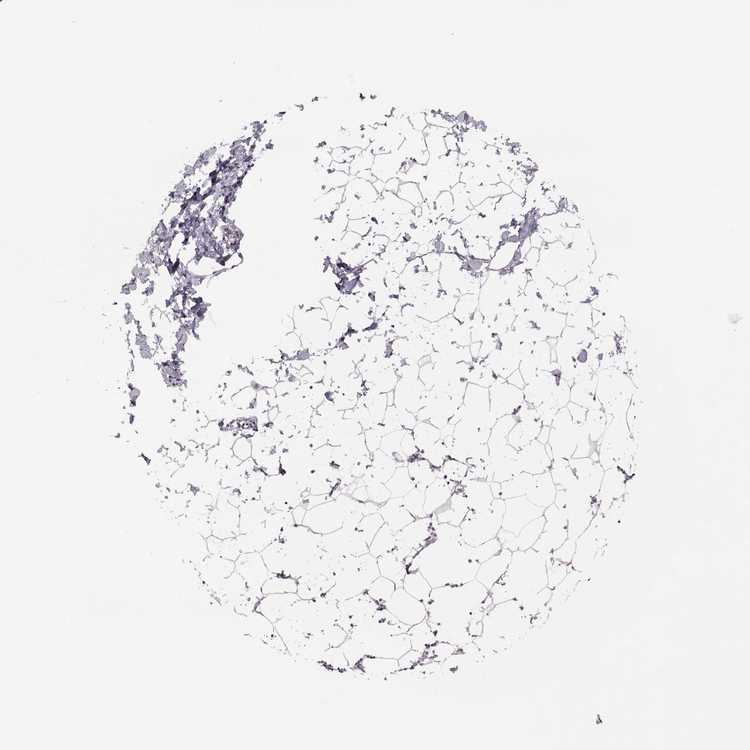

BREAST - Antibody stainingi

Antibody staining in the annotated cell types in the current human tissue is reported as not detected, low, medium, or high, based on conventional immunohistochemistry profiling in selected tissues. This score is based on the combination of the staining intensity and fraction of stained cells.

Each image is clickable and will lead to virtual microscopy that enables deeper exploration of all samples and also displays staining intensity scores, fraction scores and subcellular localization as well as patient and tissue information for each sample.

Antibody HPA030942

Adipocytes Not detected

Glandular cells Not detected

Myoepithelial cells Not detected